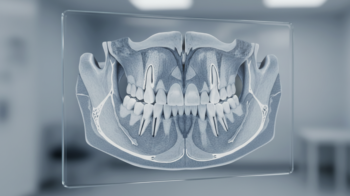

CT撮影による3D診断の重要性

従来のレントゲン撮影では平面的な情報しか得られませんでしたが、CT撮影を用いることで顎の骨を立体的に把握できます。

骨の厚み、高さ、密度、そして神経や血管の正確な位置まで確認できるため、より安全で精密な治療計画を立てることが可能です。

当院では、3Dシミュレーションを活用し、インプラントを埋入する最適な位置を事前に設計しています。

「骨のある場所にとりあえず入れる」のではなく、見た目、噛み合わせ、長期安定性まで考慮した計画的な埋入を心がけています。